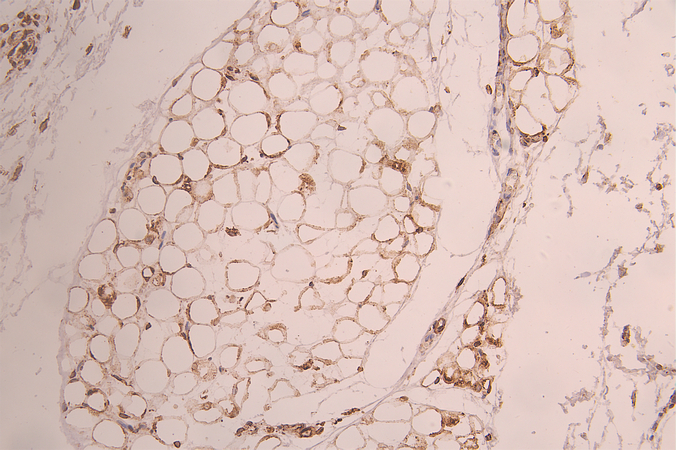

IHC image of CSB-RA889602A0HU diluted at 1:100 and staining in paraffin-embedded human skin tissue performed on a Leica BondTM system. After dewaxing and hydration, antigen retrieval was mediated by high pressure in a citrate buffer (pH 6.0). Section was blocked with 10% normal goat serum 30min at RT. Then primary antibody (1% BSA) was incubated at 4°C overnight. The primary is detected by a Goat anti-rabbit polymer IgG labeled by HRP and visualized using 0.05% DAB.